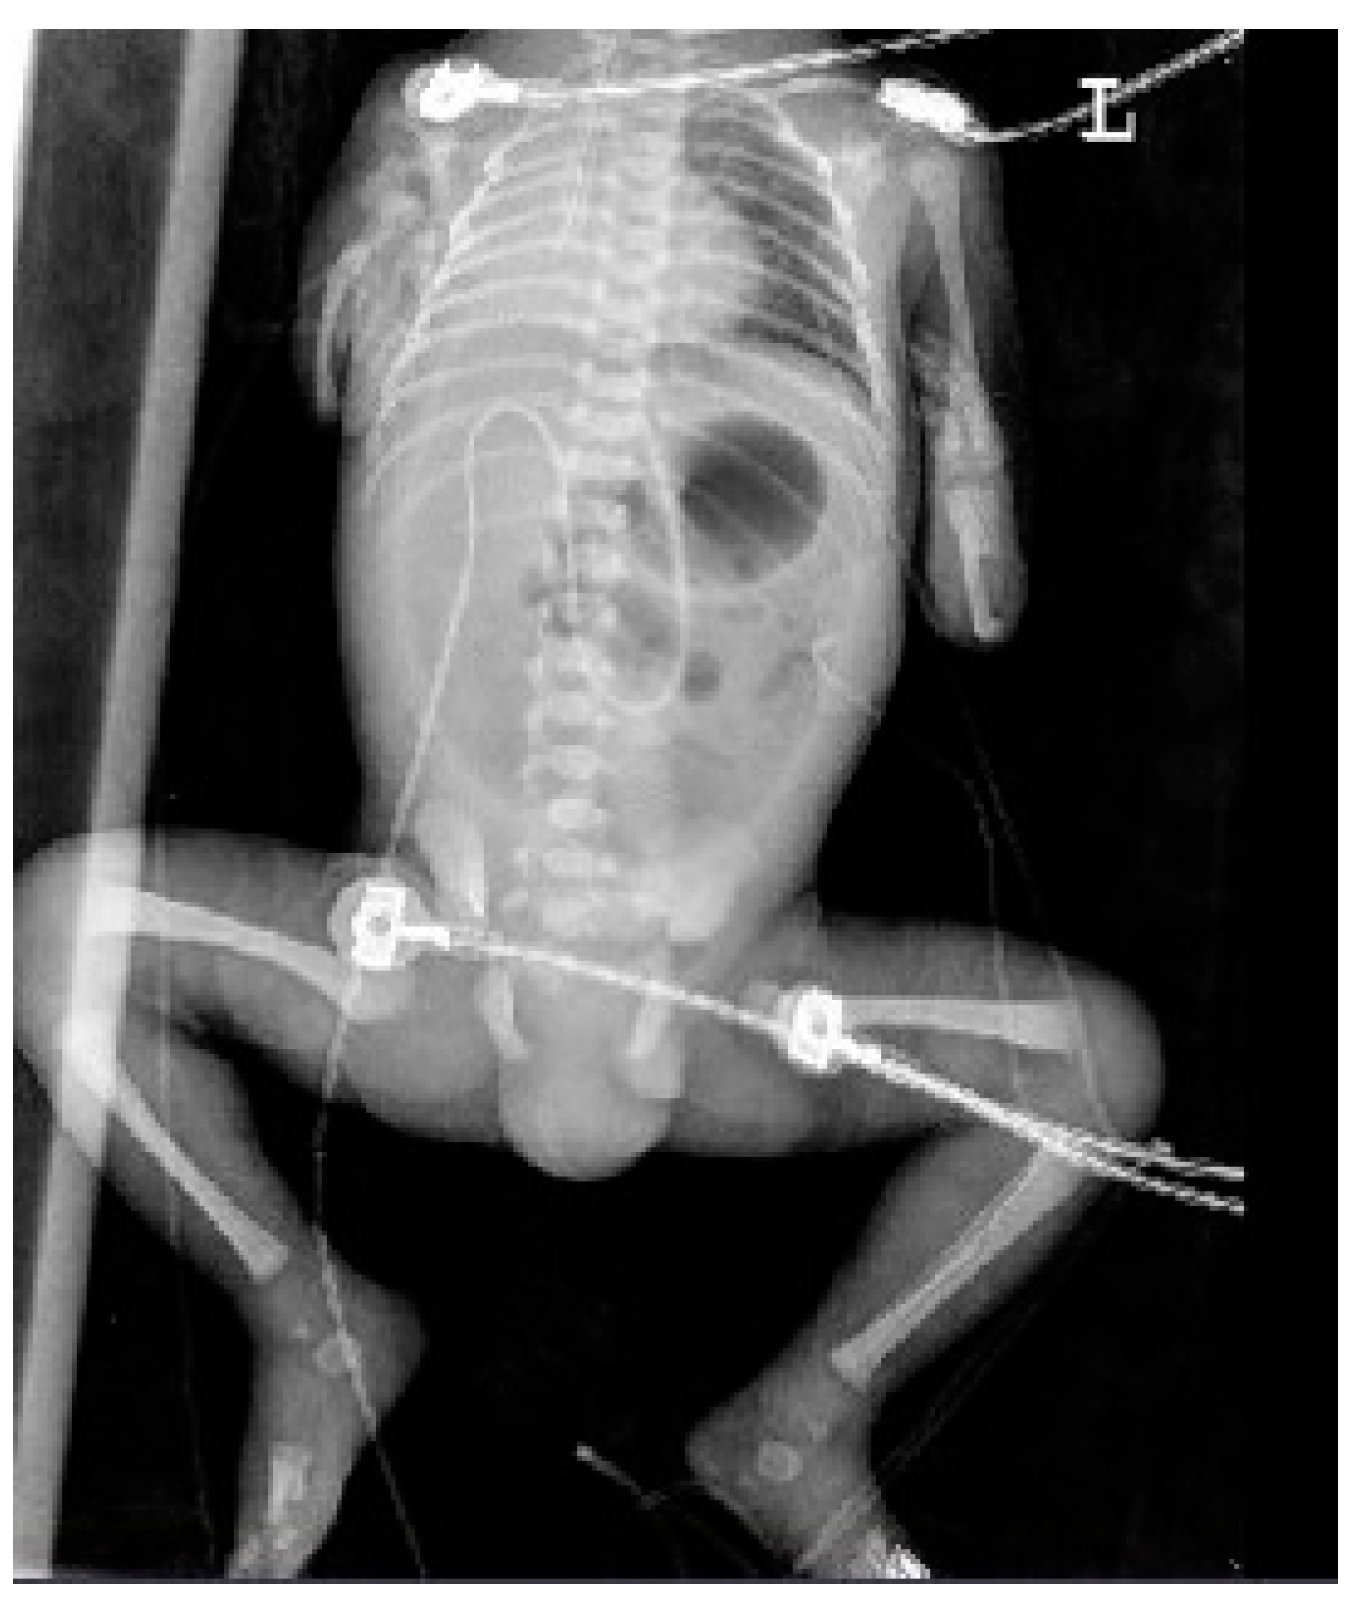

At 34 + 0 weeks gestation, an emergency cesarean delivery was performed because of relapsed preterm labor. The first baby was a male with VACTERL-H association, weighing 1390 g, and the second baby was a healthy female, weighing 1890 g. The Apgar scores at 1 and 5 min were 6 and 8 in the first twin baby and 5 and 8 in the second twin baby. The first twin had multiple anomalies diagnosed prenatally. Related imaging studies were performed, including an infantogram and 3D CT (Figure 8, Figure 9, Figure 10, Figure 11 and Figure 12). A cardiacangio 3D CT revealed dextrocardia of embryonic arrest with pulmonary hypoplasia and a tracheoesophageal fistula with a right bronchus (Figure 8). The infantogram and 3D CT showed upper-limb agenesis, which aligned with the prenatal diagnosis, including aplasia of the right proximal humerus, radial hypoplasia, and hypoplastic thumb (Figure 9, Figure 10 and Figure 11). The first twin baby also had an imperforate anus and colon dilatation (Figure 12). Neonatal echocardiography showed dextrocardia with right atrial enlargement and an interrupted inferior vena cava without major congenital cardiac abnormalities. The findings from postnatal imaging supported the prenatal diagnosis of a VACTERL-H association. On his fifth day of life, the twin baby with the VACTERL-H association died.

Figure 10. Infantogram of fetus A showing upper-limb dysplasia, pneumoperitoneum, and total atelectasis of the right lung.

Figure 11. Infantogram and 3D computed tomography showing upper-limb deformity. (A) Infantogram representing aplasia of the right proximal humerus and bilateral hypoplastic upper arm (yellow arrow). (B) 3D computed tomography representing bilateral hypoplastic thumbs (yellow arrows).